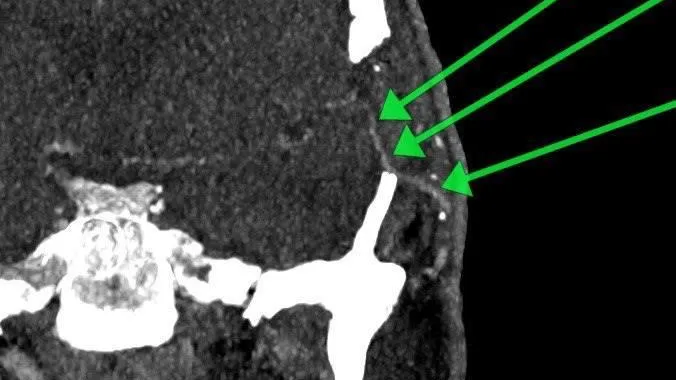

Нейрохирурги Истринской больницы спасли 59-летнего пациента, который перенес инсульт, выполнив уникальную операцию. Одна из четырех главных артерий, которые питали мозг, оказалась полностью перекрыта.

«Было принято решение наложить экстра-интракраниальный микроанастомоз — операцию по созданию обходного пути для крови. В течение почти четырех часов хирурги под микроскопом сшивали сосуды диаметром менее двух миллиметров. Тем самым, мы успешно создали для кровотока новый путь», — пояснил нейрохирург Истринской больницы Николай Карпов.

Вмешательство прошло успешно. Мужчину уже выписали. Спустя месяц после операции он прошел контрольное обследование, которое показало, что угроза миновала, а «обходной путь» работает идеально.